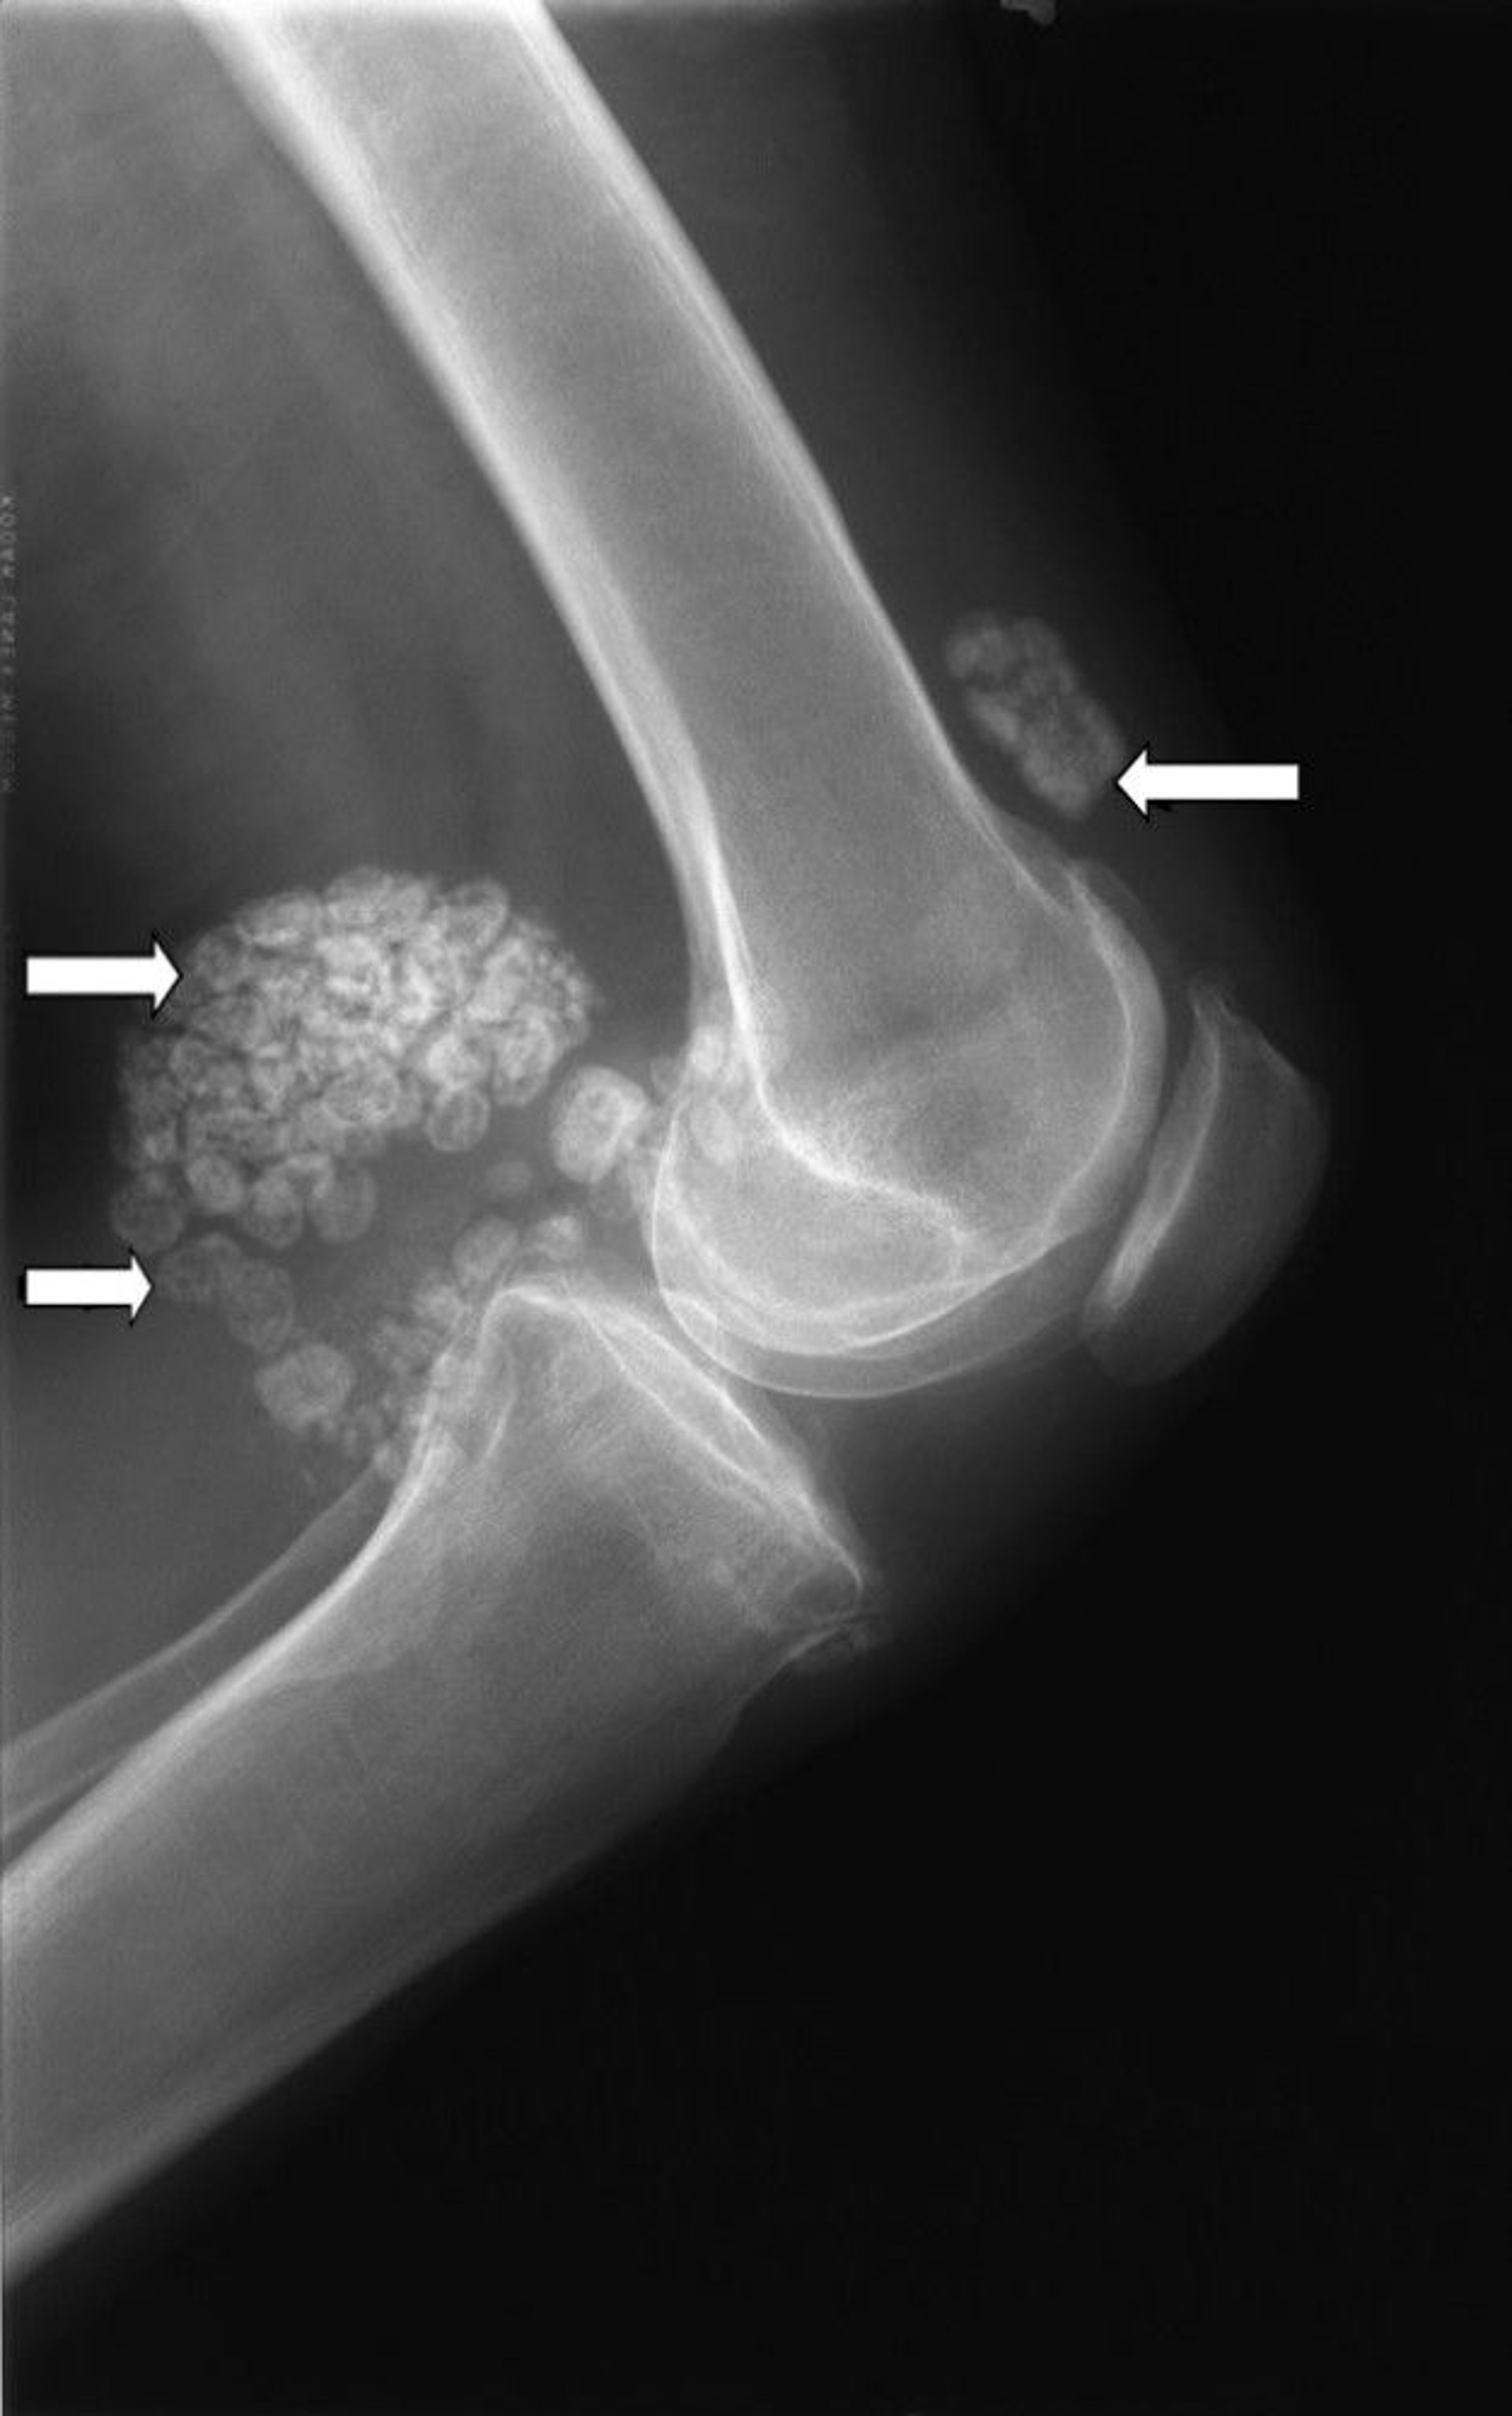

Synovial Chondromatosis

This x-ray of the knee shows multiple clumps of cartilage (arrows) known as synovial chondromatosis.

Image courtesy of Michael J. Joyce, MD, and Hakan Ilaslan, MD.